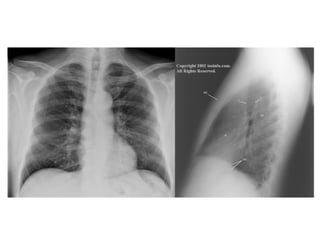

FR = 1ª costela M = manúbrio C = clavícula T = traquéia

home.comcast.net/~wnor/thoraxradiology.htm

FR = 1ªcostela M = manúbrio C = clavícula T = traquéia

Sistema Respiratório Nariz,boca, faringe, laringe, traquéia e árvore brônquica Dois pulmões

Fornecer oxigênio aosangue e às células Eliminar o dióxido de carbono do sangue Auxiliar na regulação do equilíbrio ácido-básico